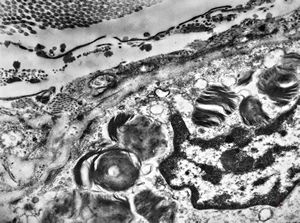

F, 24y. | molluscum contagiosum … virions

F, 24y. | molluscum contagiosum

F, 24y. | molluscum contagiosum

F, 7y. | molluscum contagiosum … virions

F, 7y. | molluscum contagiosum … virions

F, 24y. | molluscum contagiosum … virions